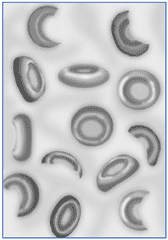

Glóbulos vermelhos danificados (esquistocitos).